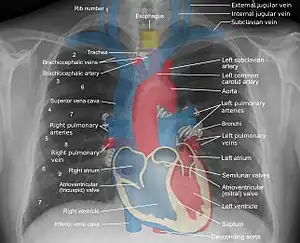

A central venous catheter (CVC), also known as a central line (c-line), central venous line, or central venous access catheter, is a catheter placed into a large vein. It is a form of venous access. Placement of larger catheters in more centrally located veins is often needed in critically ill patients, or in those requiring prolonged intravenous therapies, for more reliable vascular access. These catheters are commonly placed in veins in the neck (internal jugular vein), chest (subclavian vein or axillary vein), groin (femoral vein), or through veins in the arms (also known as a PICC line, or peripherally inserted central catheters).

During subclavian vein central line placement, the catheter can be accidentally pushed into the internal jugular vein on the same side instead of the superior vena cava. A chest x-ray is performed after insertion to rule out this possibility.[26] The tip of the catheter can also be misdirected into the contralateral (opposite side) subclavian vein in the neck, rather than into the superior vena cava.

The line is then inserted using the Seldinger technique: a blunt guidewire is passed through the needle, then the needle is removed. A dilating device may be passed over the guidewire to expand the tract. Finally, the central line itself is then passed over the guidewire, which is then removed. All the lumens of the line are aspirated (to ensure that they are all positioned inside the vein) and flushed with either saline or heparin.[1] A chest X-ray may be performed afterwards to confirm that the line is positioned inside the superior vena cava and no pneumothorax was caused inadvertently. On anteroposterior X-rays, a catheter tip between 55 and 29 mm below the level of the carina is regarded as acceptable placement.[37] Electromagnetic tracking can be used to verify tip placement and provide guidance during insertion, obviating the need for the X-ray afterwards.

The outline of superior vena cava on a chest X-ray is labeled at left.